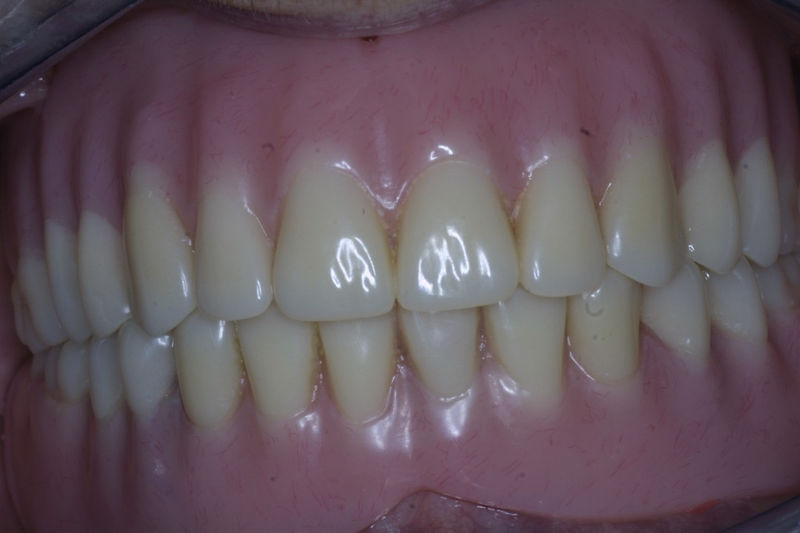

Implantes, ortodoncia y coronas.

Ortodoncia y coronas.